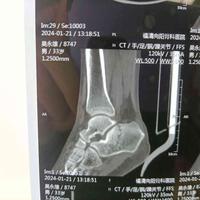

男性患者,跟骨骨折,小切口微创钢板

男性患者,跟骨骨折,小切口微创钢板...